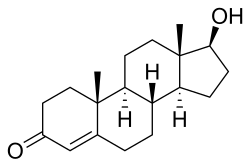

| High levels of testosterone cause hyperandrogenism | |